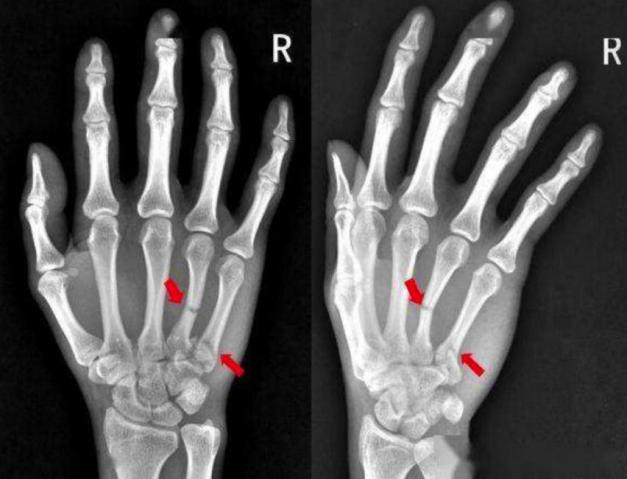

这里给大家分享一下几个图片,比如说图一是尺骨骨折,这就是一个外力直接打击造成的一个骨折形态。图二肩膀这个位置,肱骨外科颈的骨折,就是跌倒之后撑地,力纵向传导到这个部位之后,导致这个薄弱的地方造成了骨折,这就是一个间接暴力。

图片

图一                                                  图二

再看这个图三手部的掌骨骨折,这个骨折又称为拳击手骨折,为什么叫拳击手骨折呢?

图三

因为最常见的就是拳击手出现这种损伤,为什么拳击手会出现这种损伤呢?因为拳击手是在攻击,所以说这个伤就是典型的攻击伤。如果有一个人他出现这样的伤,他说我是被别人打的,那大家知道他这是打别人造成的一个骨折,而不是被别人打,被别人打是打不出这样的伤来。